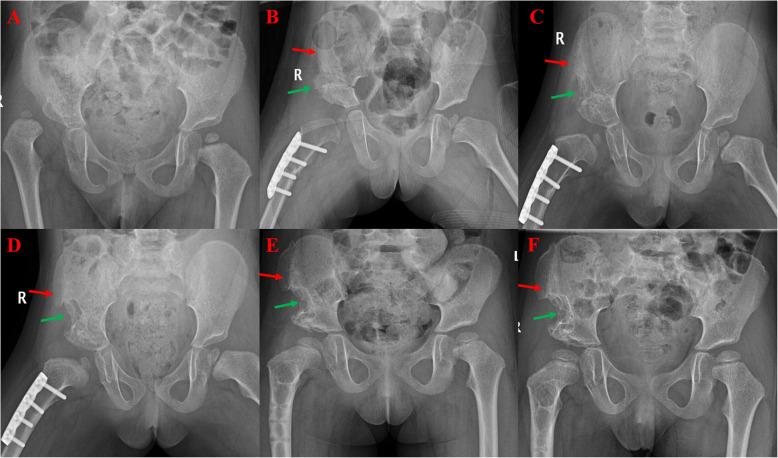

The iliac crest is one of the most used bone graft sources. In this study, we aimed to identify the effects of inner side and two-sided approaches for iliac crest bone harvesting on post-surgery ilium growth in children.

We retrospectively analyzed 47 patients who underwent pelvic osteotomy and iliac crest bone graft (ICBG) procedures from January 2015 to September 2018. The patients were divided into an inner table ilium exposure group (group A) and the inner-outer table ilium exposure group (group B) and were followed up with radiography in postoperative months 1, 3, 6, and 12, and the growth areas were measured using PACS software. Complications such as damage to the arteries or nerves, ureteral injury, gastrointestinal hernia, ileus, abnormal cosmetic appearance, sensory disturbances, and functional limitations were recorded based on clinical records.

There were 22 patients aged 5.3±1.5 years in group A and 25 patients aged 5.9±1.8 years in group B. There were no significant differences in demographics between the two groups, or in growth in the first month. However, bone graft growth at months 3, 6, and 12 was significantly better in group A than in group B. There was no significant difference in complications between the two groups.

Exposure of only the inner table of the ilium resulted in faster recovery of the bone defect than two-sided exposure in pelvic osteotomy. Therefore, we suggest protecting the outer side of the ilium during surgery.

髂嵴是最常用的骨移植来源之一。在本研究中,我们旨在确定儿童髂嵴取骨的内侧入路和双侧入路对术后髂骨生长的影响。

我们回顾性分析了2015年1月至2018年9月期间接受骨盆截骨术和髂嵴骨移植(ICBG)手术的47例患者。将患者分为内板髂骨暴露组(A组)和内外板髂骨暴露组(B组),并在术后1、3、6和12个月进行X线随访,使用PACS软件测量生长区域。根据临床记录记录动脉或神经损伤、输尿管损伤、胃肠道疝、肠梗阻、外观异常、感觉障碍和功能受限等并发症。

A组22例患者,年龄5.3±1.5岁;B组25例患者,年龄5.9±1.8岁。两组患者的人口统计学特征以及第一个月的生长情况均无显著差异。然而,A组在术后3、6和12个月时的骨移植生长情况明显优于B组。两组并发症发生率无显著差异。

在骨盆截骨术中,仅暴露髂骨内板比双侧暴露能使骨缺损恢复更快。因此,我们建议在手术过程中保护髂骨外侧。